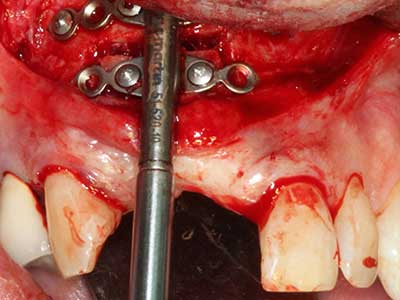

En la extracción de bloques óseos la piezocirugía también presenta ventajas adicionales: Además de la alta precisión en la osteotomía que ya se ha descrito antes, se ha comprobado que el uso de los delgados insertos de sierra resulta especialmente cuidadosas con el hueso. Frente a esto, sobre todo cuando se usan las fresas de Lindemann, cabe esperar pérdidas en la extracción significativamente más altas debido al mayor grosor de la parte frontal del cabezal (Lakshmiganthan, Gokulanathan et al. 2012). La separación basal que se necesita en particular en los injertos de bloque extraídos de forma retromolar se ve facilitada mediante sierras perpendiculares especialmente previstas a tal fin, lo que permite considerar que la cirugía piezoeléctrica es un procedimiento preciso y seguro para la obtención de bloques de hueso en el área retromolar (Happe 2007) (fig. 1-12).

Si es preciso realizar intervenciones quirúrgicas en las que el hueso está en contacto directo con estructuras sensibles, como son los vasos sanguíneos o los nervios, los instrumentos rotativos presentan un enorme potencial de provocar lesiones iatrogénicas. Así, precisamente en la representación de nervios después de una lesión iatrogénica, o en el transcurso de la lateralización de un nervio para resecciones, reconstrucciones o incorporación de implantes, los equipos piezoeléctricos pueden resultar muy útiles para preparar la tapa ósea y retirar las partes de tejido duro cercanas al nervio (fig. 17-20). Por lo general, un ligero contacto del cordón nervioso con el inserto piezoeléctrico no tiene consecuencia alguna; ahora bien, un procedimiento poco cuidadoso con movimientos tipo sierra o piezas de trabajo sobre la base ósea aún existente puede provocar lesiones nerviosas temporales o incluso permanentes. Con todo, el riesgo de sufrir una lesión de este tipo se considera significativamente inferior que en los casos en los que se utilizan sierras y fresas (Pereira, Gealh et al. 2014).